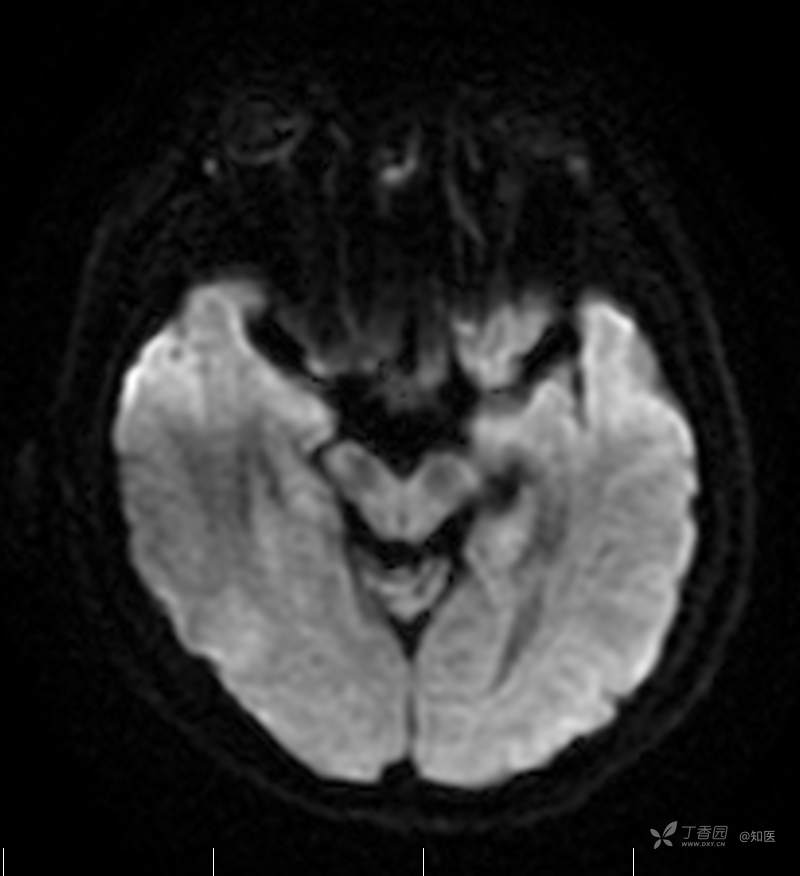

2021-6-15 DWI

2021-06-16日晨查房,患者自觉入院治疗后肢体无力症状较前稍改善,仍有活动后气短,余未诉特殊不适。ALSFRS-R评分:44分(单项均大于等于2分)。血压:123/63mmHg。神经系统查体:GCS 15分,右利手,查体合作,问答切题,粗测智能基本正常。额纹对称,双眼闭目紧,双侧瞳孔等大等圆,直径约3.0mm,对光反射灵敏,眼球运动自如,无眼震,双侧鼻唇沟对称等深,口角无歪斜。悬雍垂居中,双侧软腭抬举良好,咽反射灵敏、转颈、耸肩均一致有力。颈屈肌、颈伸肌力量5级。伸舌居中,无舌肌纤颤及萎缩。双侧岗上肌、岗下肌可见萎缩;双侧三角肌可见偶发肉跳、肌力5级,左侧肱二头肌肌力4+级、右侧4-级,双侧肱三头肌肌力4+级;双手握力可,双手大小鱼际肌及第一骨间肌可见萎缩,左侧明显,左侧手腕背伸力量4级、右侧4+级,双侧拇短展肌肌力4-级,双侧示指伸肌肌力3级,左侧指总伸肌肌力4级、右侧4-级,双侧小指展肌肌力4-级。双上肢肌张力对称减低。左侧肱二头肌反射迟钝、右侧未引出,双侧桡骨膜反射及肱三头肌反射未引出。左侧胸大肌反射阳性、右侧未引出,双侧Rossolimo征阳性、Hoffmann征阴性,下颌反射阴性。腹壁反射未引出。双下肢可见肌肉萎缩,以左侧明显;左侧髂腰肌肌力4级、右侧4-级,双侧股四头肌肌力5级,双足背伸力量3级,左足跖屈力量4级、右足4+级。双下肢肌张力对称基本正常。双侧膝腱反射、跟腱反射迟钝,双侧跖反射消失,双侧巴氏征未引出。右侧大腿外侧肌肉活检瘢痕周围浅感觉缺失,余肢体及躯干深浅感觉正常,共济运动对称正常。颈软,无抵抗,双侧布氏征及克氏征均阴性。辅助检查:微量元素(钙、镁、铁、铜、锌),微量元素测定(铅,镉)[复][2021-6-16 16:11:07]:钙1.19mmol/l;铁9.00mmol/L。急诊电解质七项[复][2021-6-16 10:41:41]:钾3.55mmol/L。血细胞分析+五分类[2021-6-16 9:57:17]:淋巴细胞百分比19.5%。[头颅,扩散成像(DWI)][头颅,磁敏感成像(SWI)][头颅,水抑制成像(FLAIR)][2021-6-16 18:10:50]:1.多发腔梗,脑白质脱髓鞘,脑萎缩。2.DWI:脑实质内未见明显高信号。3.磁敏感成像脑实质内未见明显异常信号灶。MMSE:26分(高中文化水平)。MoCA:23分。ADL评分:14分。ECAS评分:96分(ALS特异67分、ALS非特异29分)。肌电图:提示颈髓、腰髓、胸髓和延髓支配肌肉可见活动期神经源性损害,颈髓和腰髓支配肌肉同时可见慢性期神经源性损害;提示脊髓前角细胞损害可能,请结合临床。心电图大致正常。外送基因检查:TBK1基因杂合子,提示额颞叶痴呆和(或)肌萎缩性侧索硬化症4型。二线主治医师查看患者后示:1.患者基因检查结果显示TBK1基因杂合子,提示额颞叶痴呆和(或)肌萎缩侧索硬化症4型,结合外院影像学检查可见额颞叶萎缩明显,来院后复查头颅FLAIR+DWI+SWI亦提示脑萎缩,量表评估提示认知功能稍减退,ECAS评分基本正常。综上,修正诊断:肌萎缩侧索硬化症(ALS) 额颞叶变性 低钾血症 高血压2级(高危) 多发腔隙性脑梗死。因TBK1基因引起的额颞叶痴呆和(或)肌萎缩侧索硬化症为常染色体显性遗传,患者父亲已逝,母亲健在,诉无明显认知功能障碍或肌肉萎缩等表现,建议患者母亲抽血送检,进一步明确致病基因来源,必要时患者子女也可行基因检查进一步明确。2.患者目前诊断基本明确,根据文献报道,合并FTD的ALS患者整体生存周期较短(约19个月),目前患者发病已1年余,应充分与患者家属沟通病情,告知疾病预后及生存周期情况,同时建议开始口服利鲁唑片,延缓疾病进展。余治疗方案暂不予调整。密观病情变化,遵嘱执行。

2021-06-18出院总结: 卫某某,男,60岁,以“四肢僵硬1年,加重伴无力半年”之主诉入院。查体:生命体征平稳,心肺腹查体无明显异常。神经系统查体:GCS 15分,右利手,查体合作,问答切题,粗测智能基本正常。额纹对称,双眼闭目紧,双侧瞳孔等大等圆,直径约3.0mm,对光反射灵敏,眼球运动自如,无眼震,双侧鼻唇沟对称等深,口角无歪斜。悬雍垂居中,双侧软腭抬举良好,咽反射灵敏、转颈、耸肩均一致有力。颈屈肌、颈伸肌力量5级。伸舌居中,无舌肌纤颤及萎缩。左侧肱二头肌肌力4+级、右侧肱二头肌及双侧三角肌肱三头肌肌力5级;左手大小鱼际肌可见萎缩,左手握2指松、右手握力可,左手拇短展肌、示指伸肌、指总伸肌及抬腕力量3级,右手拇短展肌、示指伸肌、指总伸肌及抬腕力量4-级。双上肢肱二头肌反射、肱三头肌反射、桡骨膜反射均对称减低;双侧Hoffmann征、Rossolimo征、胸大肌反射及掌颏反射阴性,下颌反射阴性。双侧上、中、下腹壁反射可引出。左侧髂腰肌肌力4-级、右侧髂腰肌肌力4级,双侧股四头肌肌力5-级;右足背伸力量3级、左足背伸力量2级,双足跖屈力量5级。双下肢膝腱反射、跟腱反射对称减低;双侧膝阵挛、踝阵挛未引出。双侧巴氏征、Chaddock征均未引出。右侧大腿外侧肌肉活检处周围浅感觉减退,余四肢及躯干部深浅感觉正常,共济运动对称正常。颈软,无抵抗,双侧布氏征及克氏征均阴性。辅助检查:肌电图(2021-05-08,某军医大学附属医院):神经源性损害(颈段、腰骶段受累,胸段可疑;重复神经电刺激(低频、高频)可见左腋神经递减现象。 肌肉活检(2021-05-18,某军医大学附属医院):(右股四头肌)考虑神经源性损害,建议结合临床除外运动神经元病等。入院诊断:1.肢体无力:肌萎缩侧索硬化症(ALS);2.高血压1级(中危)。入院后查血清蛋白电泳:α2-球蛋白6.50%。凝血六项:血浆凝血酶原时间比值0.93;凝血酶原国际标准化比值0.93。贫血因子三项:维生素B12>1476.00pmol/L。平诊肝功十三项+平诊心肌酶谱五项+血同型半胱氨酸测定+平诊血脂八项+平诊肾功七项+平诊电解质八项:尿素3.05mmol/L;肌酐49umol/L;钾3.15mmol/L;高密度脂蛋白0.99mmol/L;载脂蛋白A1.131g/L;脂蛋白(a)333mg/L;肌酸激酶420U/L;总胆红素22.1umol/L;直接胆红素5.4umol/L。微量元素(钙、镁、铁、铜、锌),微量元素测定(铅,镉):钙1.19mmol/l;铁9.00mmol/L。急诊电解质七项:钾3.55mmol/L。血细胞分析+五分类:淋巴细胞百分比19.5%。[头颅,扩散成像(DWI)][头颅,磁敏感成像(SWI)][头颅,水抑制成像(FLAIR)]:1.多发腔梗,脑白质脱髓鞘,脑萎缩。2.DWI:脑实质内未见明显高信号。3.磁敏感成像脑实质内未见明显异常信号灶。MMSE:26分(高中文化水平)。MoCA:23分。ADL评分:14分。肌电图:提示颈髓、腰髓、胸髓和延髓支配肌肉可见活动期神经源性损害,颈髓和腰髓支配肌肉同时可见慢性期神经源性损害;提示脊髓前角细胞损害可能。血尿粪常规、免疫八项、风湿三项、血沉、传染指标、血同型半胱氨酸、糖化血红蛋白等未见明显异常。心电图、肺通气功能大致正常。住院期间给予营养神经、清除氧自由基等对症支持治疗。现患者诊断基本明确,生命体征平稳,一般情况良好,可予今日出院。出院诊断:1.肌萎缩侧索硬化症(ALS);2.额颞叶变性;3.低钾血症;4.高血压2级(高危);5.多发腔隙性脑梗死。出院医嘱:1.注意休息,加强营养,低盐、高蛋白高纤维素饮食,注意休息,适当锻炼,避免剧烈运动及重体力劳动。2.出院继续口服药物:甲钴胺 500ug/次,3次/日;辅酶Q10 10mg/次,3次/日;维生素E 100mg/次,2次/日;美金刚 10mg/次,1次/日;利鲁唑片,50mg/次,2次/日,与餐间隔1.5-2小时。3.出院继续用依达拉奉(必存)60mg+0.9%氯化钠 200ml,静滴,1次/日(首疗程14天,后每疗程10天,间隔20天,共使用6个疗程)。4.1月后门诊复查血常规、肝肾功能、电解质功能;3月后我科门诊再次复诊。5.不适随诊。